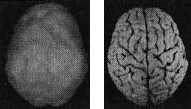

Когда мозг работает правильно, у вас все хорошо Когда мозг не в порядке, в жизни начинаются неприятности Именно мозг определяет эффективность вашей жизни. Этот принцип выглядит простым, но на самом деле он достаточно неоднозначный и может вызвать тревожность. Основная идея заключается в том, что мозг должен функционировать оптимально. Когда он работает правильно, вам легче оставаться эффективным родителем, ребенком, партнером, другом, коллегой, менеджером или общественным деятелем. Когда мозг функционирует правильно, вы имеете полный доступ к своему истинному Я. С другой стороны, если мозг болен, начинаются трудности в работе, отношениях, наедине с собой и в компаниях. Становится труднее проявлять свои лучшие качества и сильные стороны, нередко люди действуют вопреки своим ценностям, целям и представлениям о нравственности. Принцип 2 Когда мозг работает правильно, у вас все хорошо. Когда мозг не в порядке, в жизни начинаются неприятности Я вывел этот принцип в результате интерпретации сотен томограмм моих пациентов, поскольку не только читаю сканы, но и напрямую работаю с людьми и их семьями, изучаю историю их жизней. Уже в самом начале моей работы с томографией стало очевидно, что существует зависимость между качеством функций мозга на сканограммах и умением моих пациентов принимать решения, ставить цели и поддерживать отношения. Анализируя снимки, я стал размышлять о разнице между двумя типами поведения, которые я называю волевым поведением (управляемым силой воли) и мозговым поведением (управляемым неконтролируемыми импульсами мозга). Реализовывать команды силы воли возможно только при здоровом мозге, поскольку лишь он позволяет людям делать осознанный выбор и в любой ситуации действовать себе во благо. Волевое поведение продуктивно, оно способствует достижению целей, которые вы сами поставили. Например, приняв решение поступить в медицинский институт, человек должен очень усердно учиться, чтобы выдержать сложные экзамены. Прежде чем объяснить, что такое «мозговое поведение», я хочу сделать небольшое отступление, чтобы рассказать о томографии, которую мы проводим в наших клиниках. Она называется ОЭКТ — однофотонная эмиссионная компьютерная томография — и относится к области ядерной медицины, то есть для оценки кровообращения и схем активности мозга используются крошечные дозы радиоизотопов. Сканограммы ОЭКТ отличаются от типичных анатомических снимков МРТ и КАТ, которые показывают строение мозга. ОЭКТ показывает только степень активности разных областей мозга — то, как он работает. Результаты сканов ОЭКТ очень легко интерпретировать. Нужно посмотреть на области мозга, которые работают хорошо, области, которые функционируют чересчур активно («перегреты») и на недостаточно активные области. Затем мы сравниваем изучаемый скан с большой базой данных здоровых и абнормальных томограмм. В этой книге используют трехмерные снимки мозга двух видов. Первый — это трехмерные снимки поверхности, которые фиксируют верхние 45 % активности мозга. На них показано кровообращение в коре мозга и подкорковых областях. По этим снимкам мы определяем области нормального кровообращения и области со сниженным доступом крови. С помощью таких томограмм выявляют инсульты, травмы и ущерб от наркотиков. Снимок здорового мозга должен показать ровную симметричную активность по всей поверхности коры мозга (рис. 2.1 и 2.2). Трехмерное изображение поверхности здорового мозга ОЭКТ (вид поверхности сверху и снизу) Рис. 2.1 Вид сверху Полная симметричная активность ![]() Рис. 2.2 Вид снизу Полная симметричная активность ![]() Сниженная активность выглядит на подобных сканах как дыра или вмятина. Эти «дыры» и «провалы» не означают, что активность мозга в этих местах совсем на нуле, она просто снижена, так как компьютер настроен показывать только верхние 45 % активности. Все, что меньше этого значения, выглядит как дыра или вмятина. Порог в 45 % выбран, поскольку он соответствует двум стандартным отклонениям от нормы [1] и, согласно нашим данным и данным других исследователей, является оптимальным для диагностических целей. Второй тип томограмм — это трехмерные функциональные снимки, в которых компьютер сначала вычисляет среднюю активность мозга, а затем показывает верхние 15 % активности. Они помогают увидеть гиперактивные области, что полезно в диагностике припадков, разных типов тревожности и депрессии. Здоровый трехмерный функциональный снимок (рис. 2.3 и 2.4) должен показывать активность (белым цветом) в задней части мозга (мозжечке) и визуальной, или затылочной, коре и среднюю активность в остальных местах (показано сеткой). Трехмерное изображение функциональной активности здорового мозга ОЭКТ (вид поверхности сверху и снизу) Рис. 2.3 Вид сверху ![]() Рис. 2.4 Вид сверху ![]() Примечание: В тексте книги будут использоваться иконки, которые помогут читателю понимать сканограммы и увидеть их отличия от нормы. Рис. А состоит из двух иконок: трехмерного изображения поверхности здорового мозга, вид сверху; и модели мозга с той же самой перспективы. ![]() Рис. Б показывает трехмерный снимок поверхности здорового мозга, вид снизу, а нижняя иконка — это модель мозга с той же перспективы. ![]() Рис. В показывает трехмерную картину активности здорового мозга, вид сверху, а ниже показан мозг в этой проекции. ![]() |